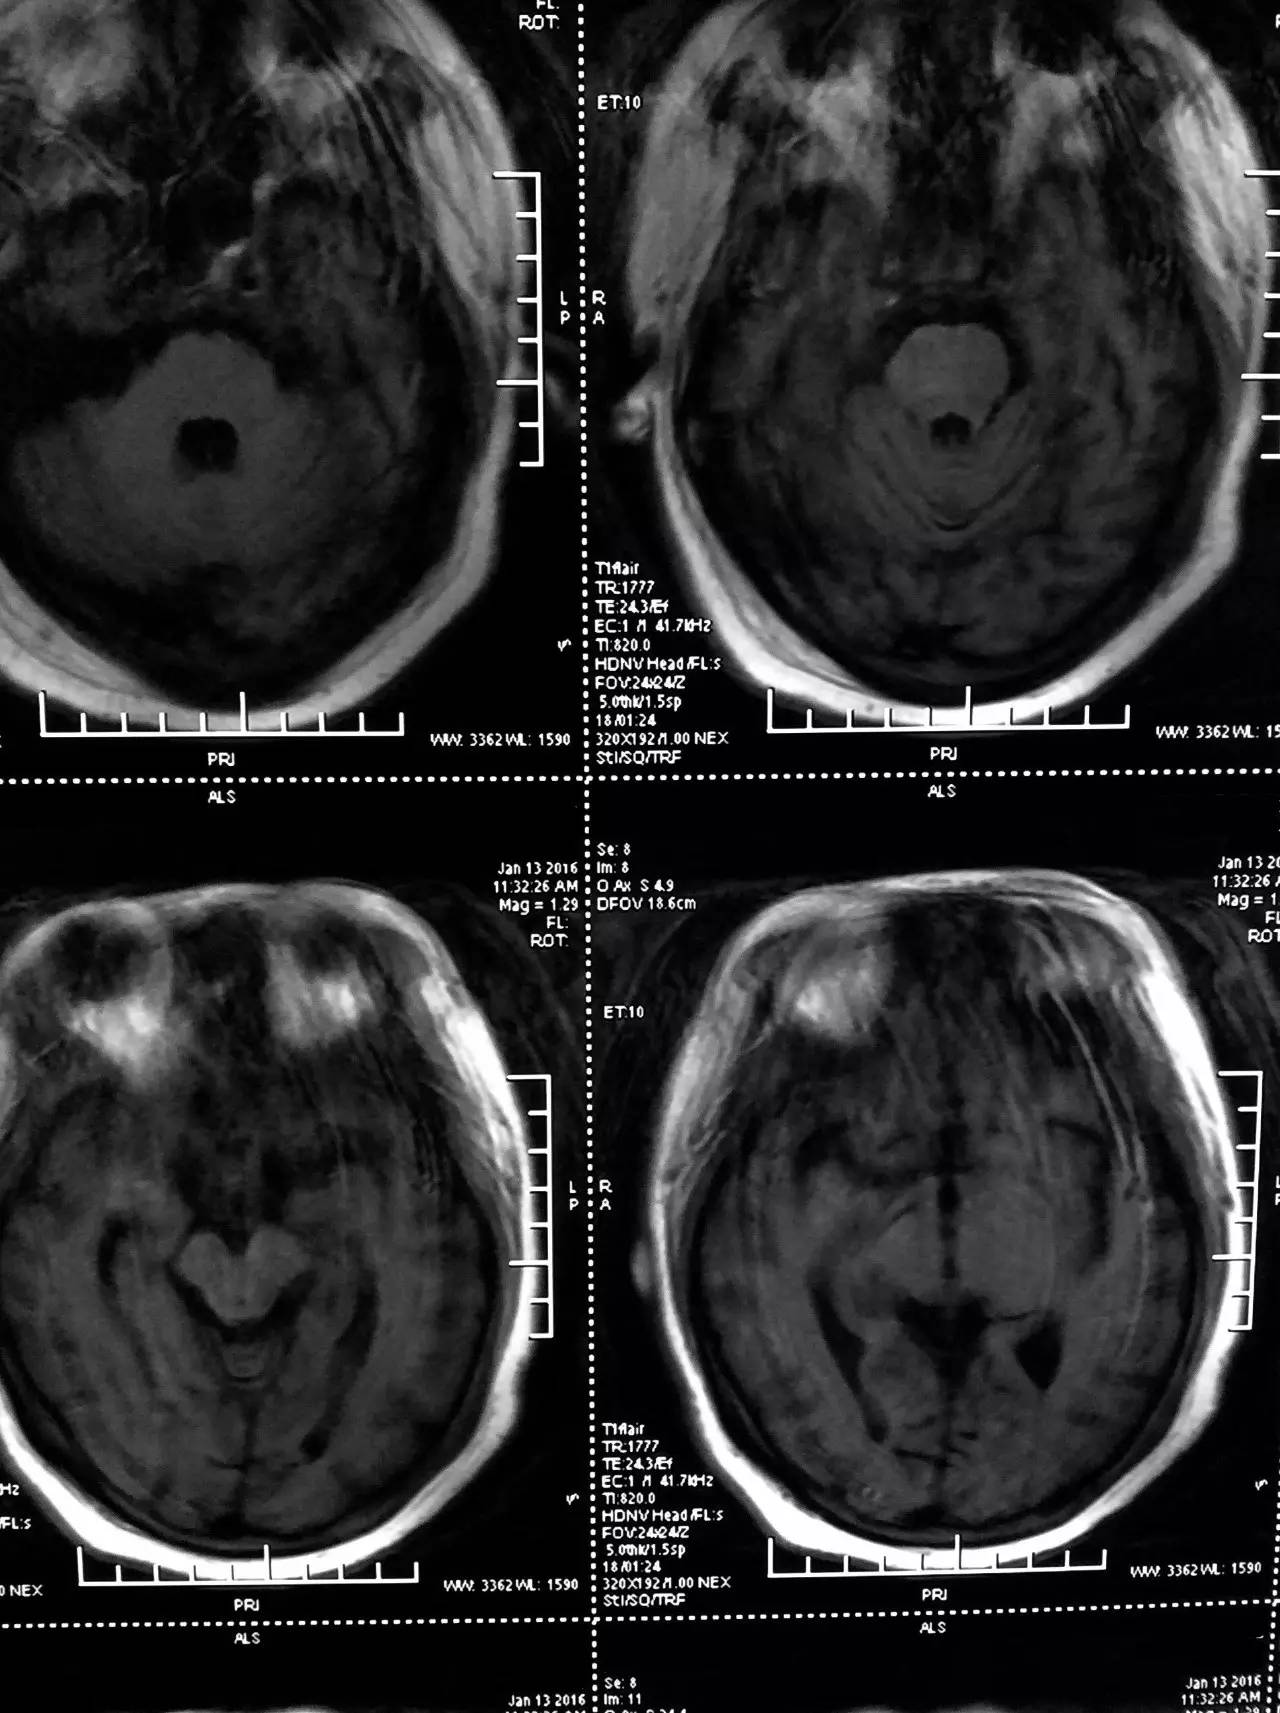

▼患者影像资料